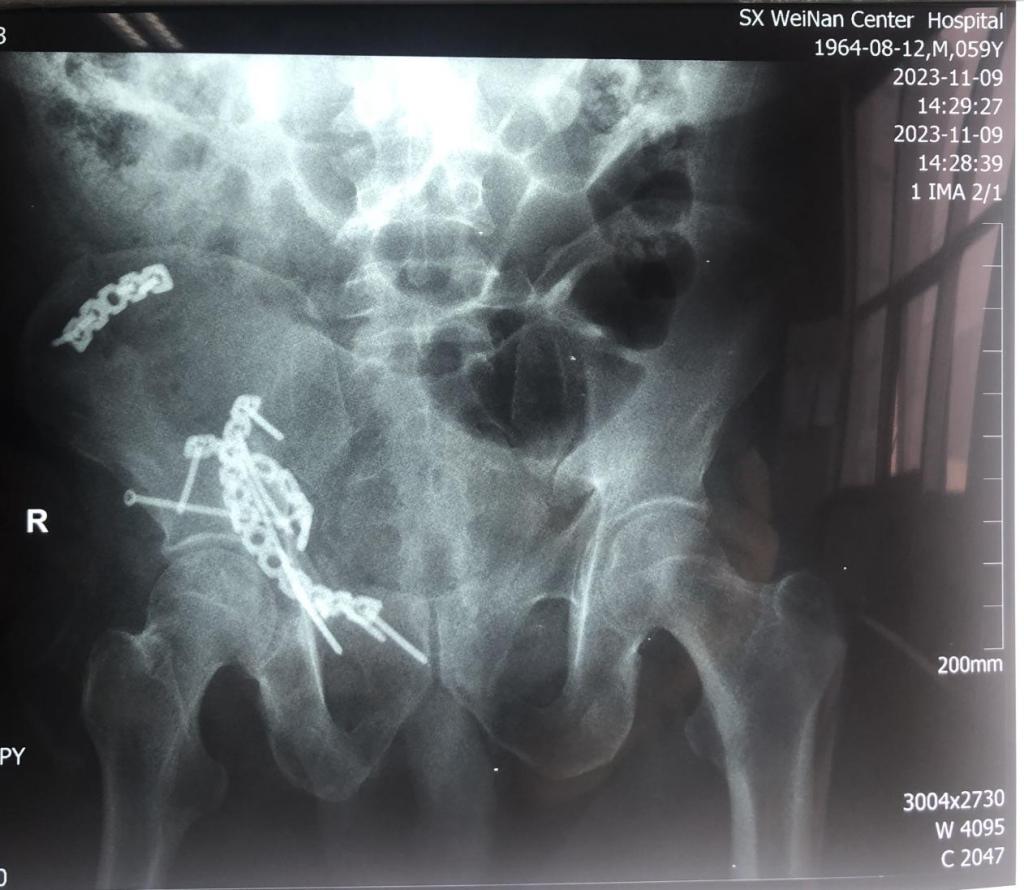

患者车祸致伤入院后,李玉民主任医师组织科内多次讨论认为,该患者为高能量损伤致复杂髋臼骨折,Letournel-Judet分型为高位前柱伴后半横骨折,股骨头中心脱位致臼顶、四方体粉碎性骨折,后柱横断向后方移位,前柱高位骨折伴旋转移位,头臼不匹配,臼内台阶明显,髋关节失去正常形态,失去明显的解剖标志,严重功能受限。须尽早积极手术治疗,否则后期出现畸形愈合关节功能丧失,股骨头坏死,致残率增高失去劳动能力。

经严谨的术前规划及方案设计,11月7号由郭宏军主任医师医疗组给予单一前方经腹直肌旁入路手术内固定。术后患者右髋关节功能恢复良好,自行翻身,半靠体位均不受限。

该患者伤后三周手术,骨折端已明显骨痂包绕,显露不易,术后给予高位前柱截骨使得髋臼骨折易于解剖复位固定,恢复了髋臼关节面光滑连续完整,头臼匹配良好,预防了股骨头后期坏死,使患者能够早期功能锻炼,最大程度减少了致残率,早日恢复劳动力。